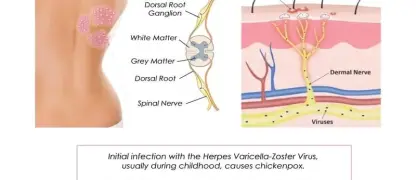

Visualizing concepts related to CTE